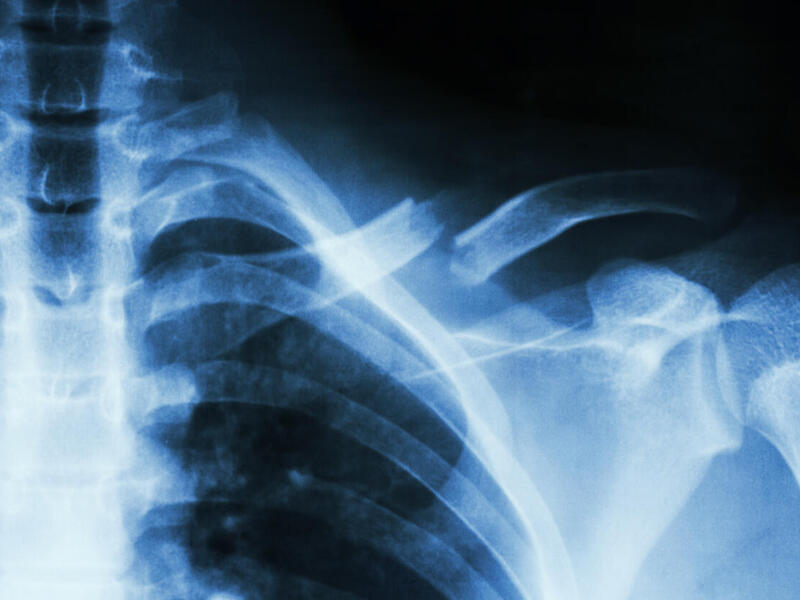

Individuals with spinal cord injury and resulting lower limb paralysis can retain some independence by using manual wheelchairs, but up to 84 percent of patients who use them develop shoulder pain associated with overuse injuries.

Researchers have discovered a difference between individuals with spinal cord injuries who began using manual wheelchairs as children and those injured as adults. Despite more years of wheelchair use, adults with pediatric onset actually have less shoulder pain, said Carrie Peterson, Ph.D., an assistant professor in the Department of Biomedical Engineering in VCU’s College of Engineering.

Peterson is researching how to improve health and quality of life for individuals with spinal cord injury who use manual wheelchairs — from childhood through adulthood. She is part of a team led by researchers at the University of Wisconsin-Milwaukee that has received a $2.5 million grant from the Eunice Kennedy Shriver National Institute of Child Health and Human Development at the National Institutes of Health. The four-year study is aimed at disease prevention for individuals with spinal cord injury through the use of advanced biomechanical modeling and diagnostic imaging.

Peterson, who will receive $413,544 under the grant, will generate computational simulations of musculoskeletal dynamics during wheelchair propulsion to quantify shoulder joint contact forces.

“The goal of the project is to determine whether the movement variability reduces the shoulder joint demands, and therefore leads to decreased shoulder pain and progressive pathology,” she said.

The long-term goal is to develop rehabilitation strategies to prevent and treat symptoms of shoulder loading and overuse contributing to shoulder pain by creating guidelines for children and improving those for adults